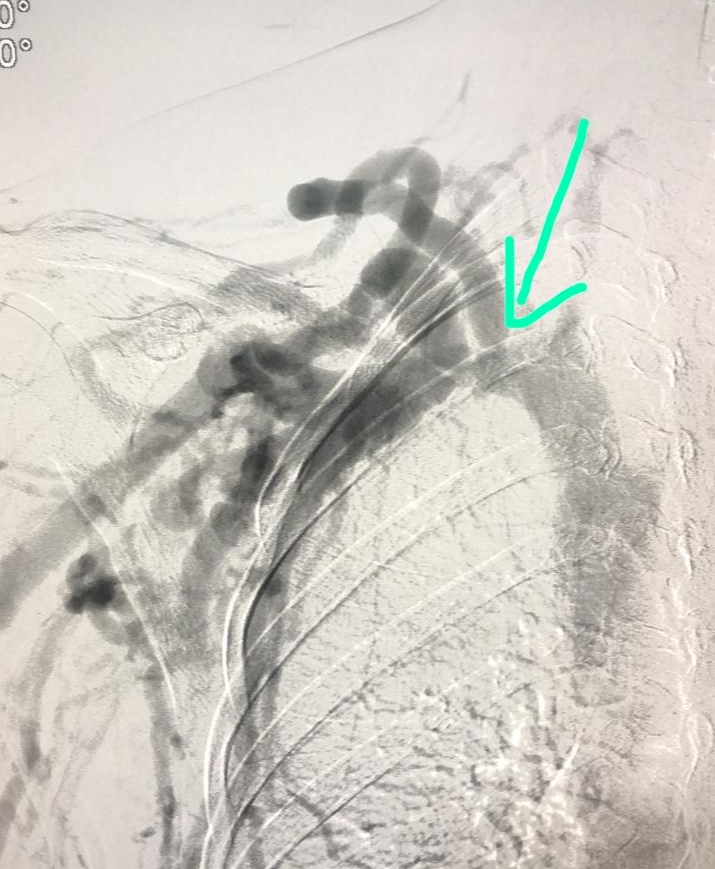

CENTRAL VENOUS OCCLUSION. BRACHIOCEPHALIC FISTULA.

A 28 year-old female ESRD patient with brachiocephalic aneurysmatic fistula (8 months). Right arm with important edema, painful. Very short subclavian occlusion, three hours trying cross the occlusion with a lot of guidewires, microcatheters by femoral and fistula way. No good outcomes. More endovascular options? Very frustrating case.